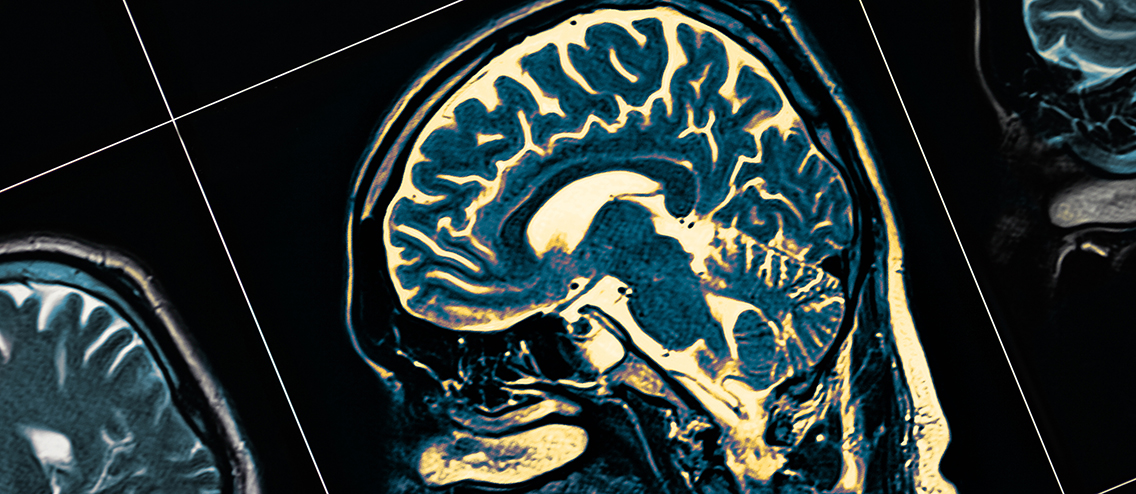

Veränderungen der Hirnstruktur im Langzeitverlauf bei nicht-hospitalisierten Personen

Anhand von Daten der in der prä-Pandemie-Ära begonnenen, longitudinal angelegten „UK Biobank“ konnten erstmals zerebrale MRT-Befunde vor und nach COVID-19 bei denselben Personen erhoben und mit einer Kontrollgruppe Nicht-Infizierter verglichen werden [1]. Im Ergebnis zeigte sich bei den zwischenzeitlich SARS-CoV-2-Infizierten ein Rückgang an grauer Substanz im orbitofrontalen Kortex sowie eine Abnahme der Gesamthirnmasse. Bei den Betroffenen verschlechterten sich im Verlauf auch die kognitiven Testergebnisse. Ob diese Veränderungen reversibel sind, ist derzeit noch offen. Eine weitere Studie [2] zeigte eine erhöhte Rate an de novo-Demenzen nach COVID-19 im Vergleich zu anderen Pneumonien.